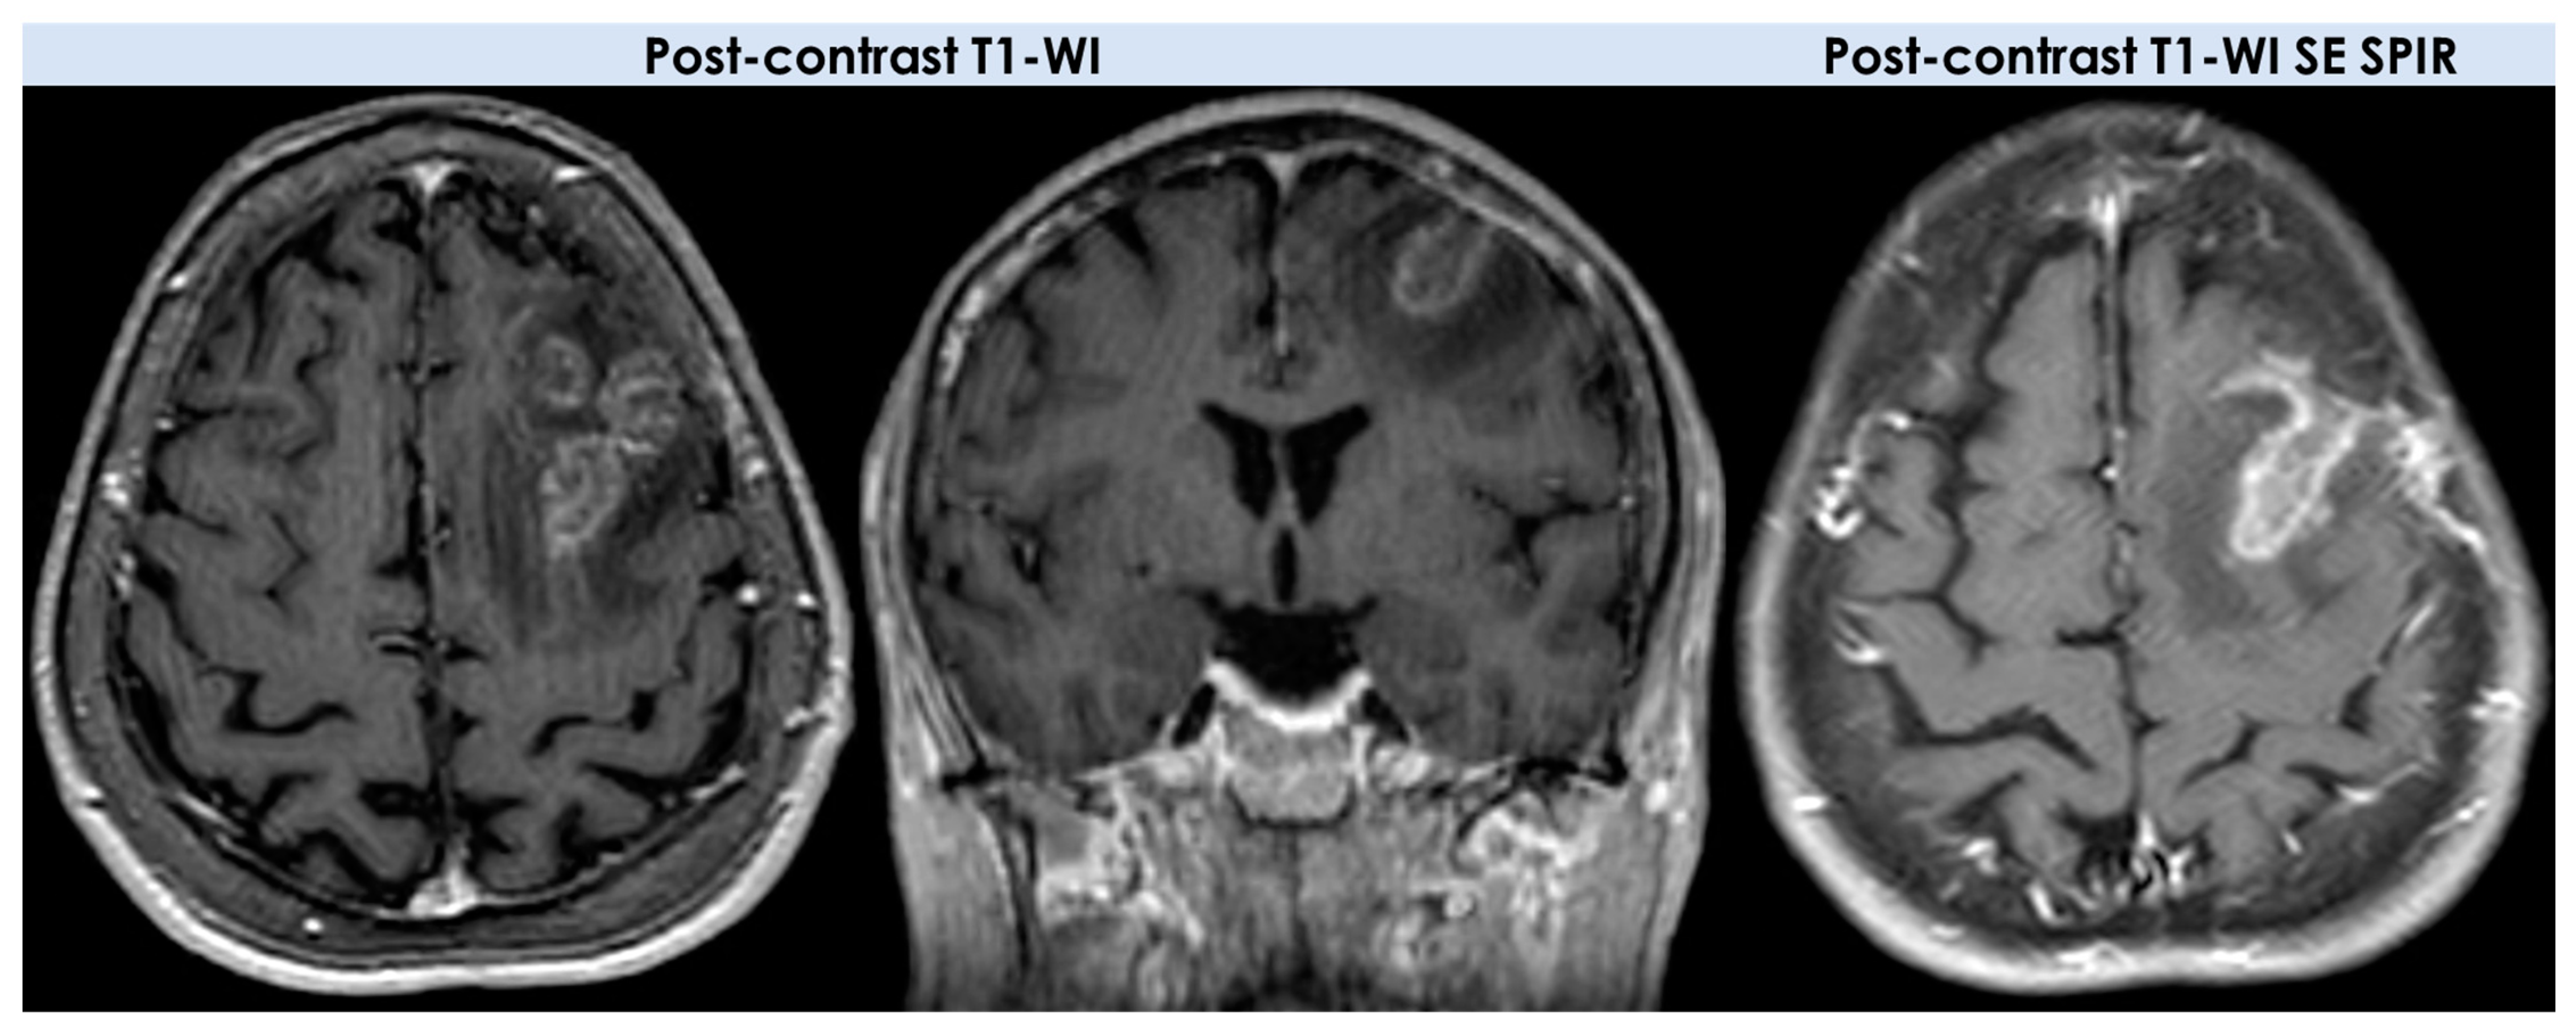

- Enhancement patterns (parenchyma): all patients (10/10, 100%) had enhancing lesions with patchy parenchymal pattern in 5/10 (50%), “mottled appearance” (multiple small hypoenhancing areas within the patchy enhancing masses) in 3/10, small nodular pattern in 5/10, ring enhancement in 2/10, and linear (perivascular) enhancement pattern in 1/10 patients;

- Enhancement patterns (leptomeninges): localized leptomeningeal enhancement adjacent to the dominant/largest lesions was found in 4/10 patients (40%), localized subependymal enhancement adjacent to the lesions in 3/10 patients (30%); and diffuse leptomeningeal or subependymal enhancement was not documented;